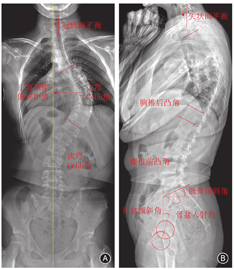

侧凸Cobb角定义为冠状面头侧端椎上终板与尾侧端椎下终板所成的夹角(图1)。Cobb角最大的侧弯为主弯,其次的侧弯为次弯。Cobb角越大表示侧凸畸形越严重。柔韧性可预测病变脊柱的可塑性和弹性,通过以下公式[20]计算:

2.顶椎偏移距离(apical vertebral translation, AVT),是评估脊柱侧凸的常用指标,对制定手术策略、预测术后并发症等具有重要的指导意义。评估上胸弯和胸弯时,定义为顶椎或顶椎间盘中点至C7铅垂线的水平距离;评估胸腰弯和腰弯,定义为顶椎或顶椎间盘中点至骶骨中垂线的水平距离(图1)。

3.冠状面平衡(coronal balance, CB):定义为C7铅垂线(C7 plumb line,C7PL)至骶骨中垂线(center sacral vertical line,CSVL)的水平距离(图1)。CB >20 mm定义为冠状面失衡 [21]。

1.胸椎后凸角(thoracic kyphosis,TK):定义为T3椎体上终板与T12椎体下终板的夹角(图1)。根据正常人群矢状面参数将TK分为后凸正常(20°~50°)、后凸减小(< 20°)和后凸增大(>50°)[17,22]。

2.腰椎前凸角(lumbar lordosis,LL):定义为T12与S1上终板的夹角(图1)。根据正常人群矢状面参数将LL分为前凸正常(54°~74°)、前凸减小(< 54°)和前凸增大(>74°)[17,22]。

3.骨盆倾斜角(pelvic tilt,PT),是骨盆的位置参数,描述骨盆旋转的情况,反映代偿机制。定义为经骶骨上终板中点和双侧股骨头中心连线中点连线与铅垂线的夹角(图1)。

4.骨盆入射角(pelvic incidence,PI),是骨盆的解剖学参数,反映骨盆对矢状面失衡的代偿能力。定义为经骶骨上终板中点的垂线与经骶骨上终板中点和双侧股骨头中心连线中点连线的夹角(图1)。

5.骶骨倾斜角(sacral slope,SS),是骨盆的位置参数,PT和SS共同用于描述骨盆绕股骨头旋转的情况。定义为骶骨上终板切线与水平线的夹角(图1),与PT、PI之间存在如下等量关系,即PI=PT+SS。

6.矢状面平衡(sagittal vertical axis,SVA):定义为C7铅垂线(C7PL)至骶骨后上角的水平距离(图1)。SVA>50 mm定义为矢状面失衡[20]。